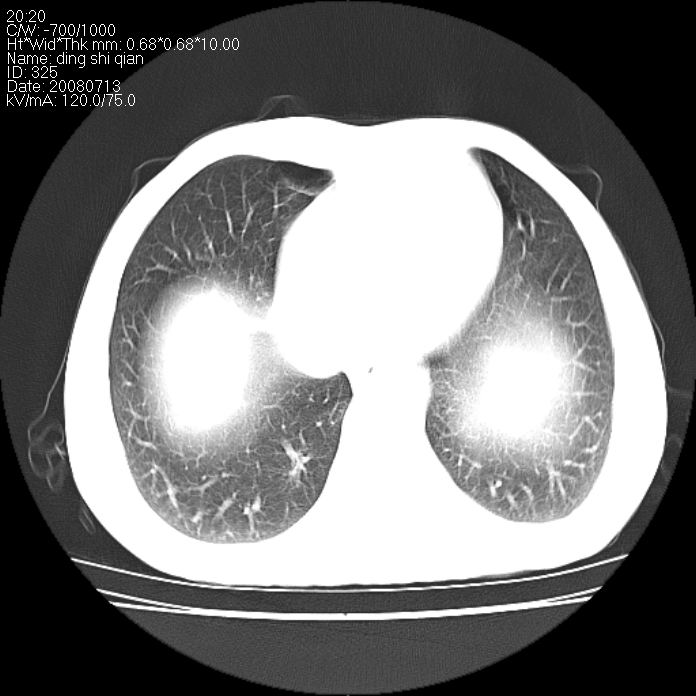

右侧上肺块状软组织影,浅分叶,边缘毛刺证,与胸膜粘连,考虑:周围性肺癌

右侧上肺块状软组织影,浅分叶,边缘毛刺证,与胸膜粘连,考虑:周围性肺癌!支持!

典型右肺周围型肺癌

首先考虑周围性肺癌,建议强化或穿刺明确

右肺上叶周围型肺癌。

右肺上叶周围型肺癌可能性大。